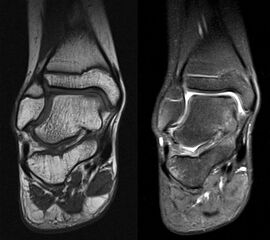

MRT

Die Kernspintomographie hat ihre Stärke in der Darstellung von Weichteilverletzungen. Insbesondere Verletzungen der Wachstumsfuge, des Periosts und der Bänder lassen sich gut visualisieren. Nachteilig ist die Untersuchungsdauer von 20-30 Minuten. Bleibt das Kind während dieser Zeit nicht ruhig liegen, kommt es zu Bewegungsartefakten, welche die Beurteilbarkeit der Bilder beeinträchtigen.

• Einblutung und Ödemzone im MRT

Ossifikationsstörung des Talus

Manchmal findet sich an der talaren Gelenksfläche eine lokale Störung der Ossifikationen. Wichtigste Differenzialdiagnose ist die osteochondrale Läsion. Die Ossifikationsstörung ist ein Zufallsbefund ohne klinische Relevanz. Kennzeichnend sind das fehlende Ödem und die intakte Knorpeloberfläche.